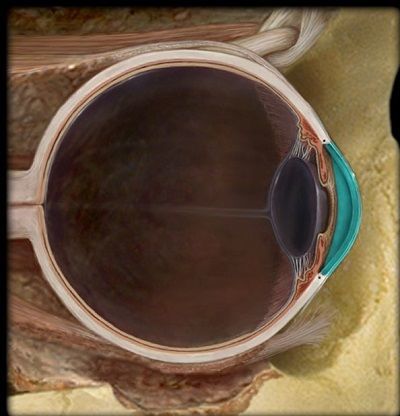

Question 1

Question

¿Qué estructura esta señalada?

Image:

0795d8bb-2212-47aa-a113-e11cb62a3603 (image/jpeg)

Answer

Cornea

Iris

Pupila

Cristalino

N. Optico

D. Optico